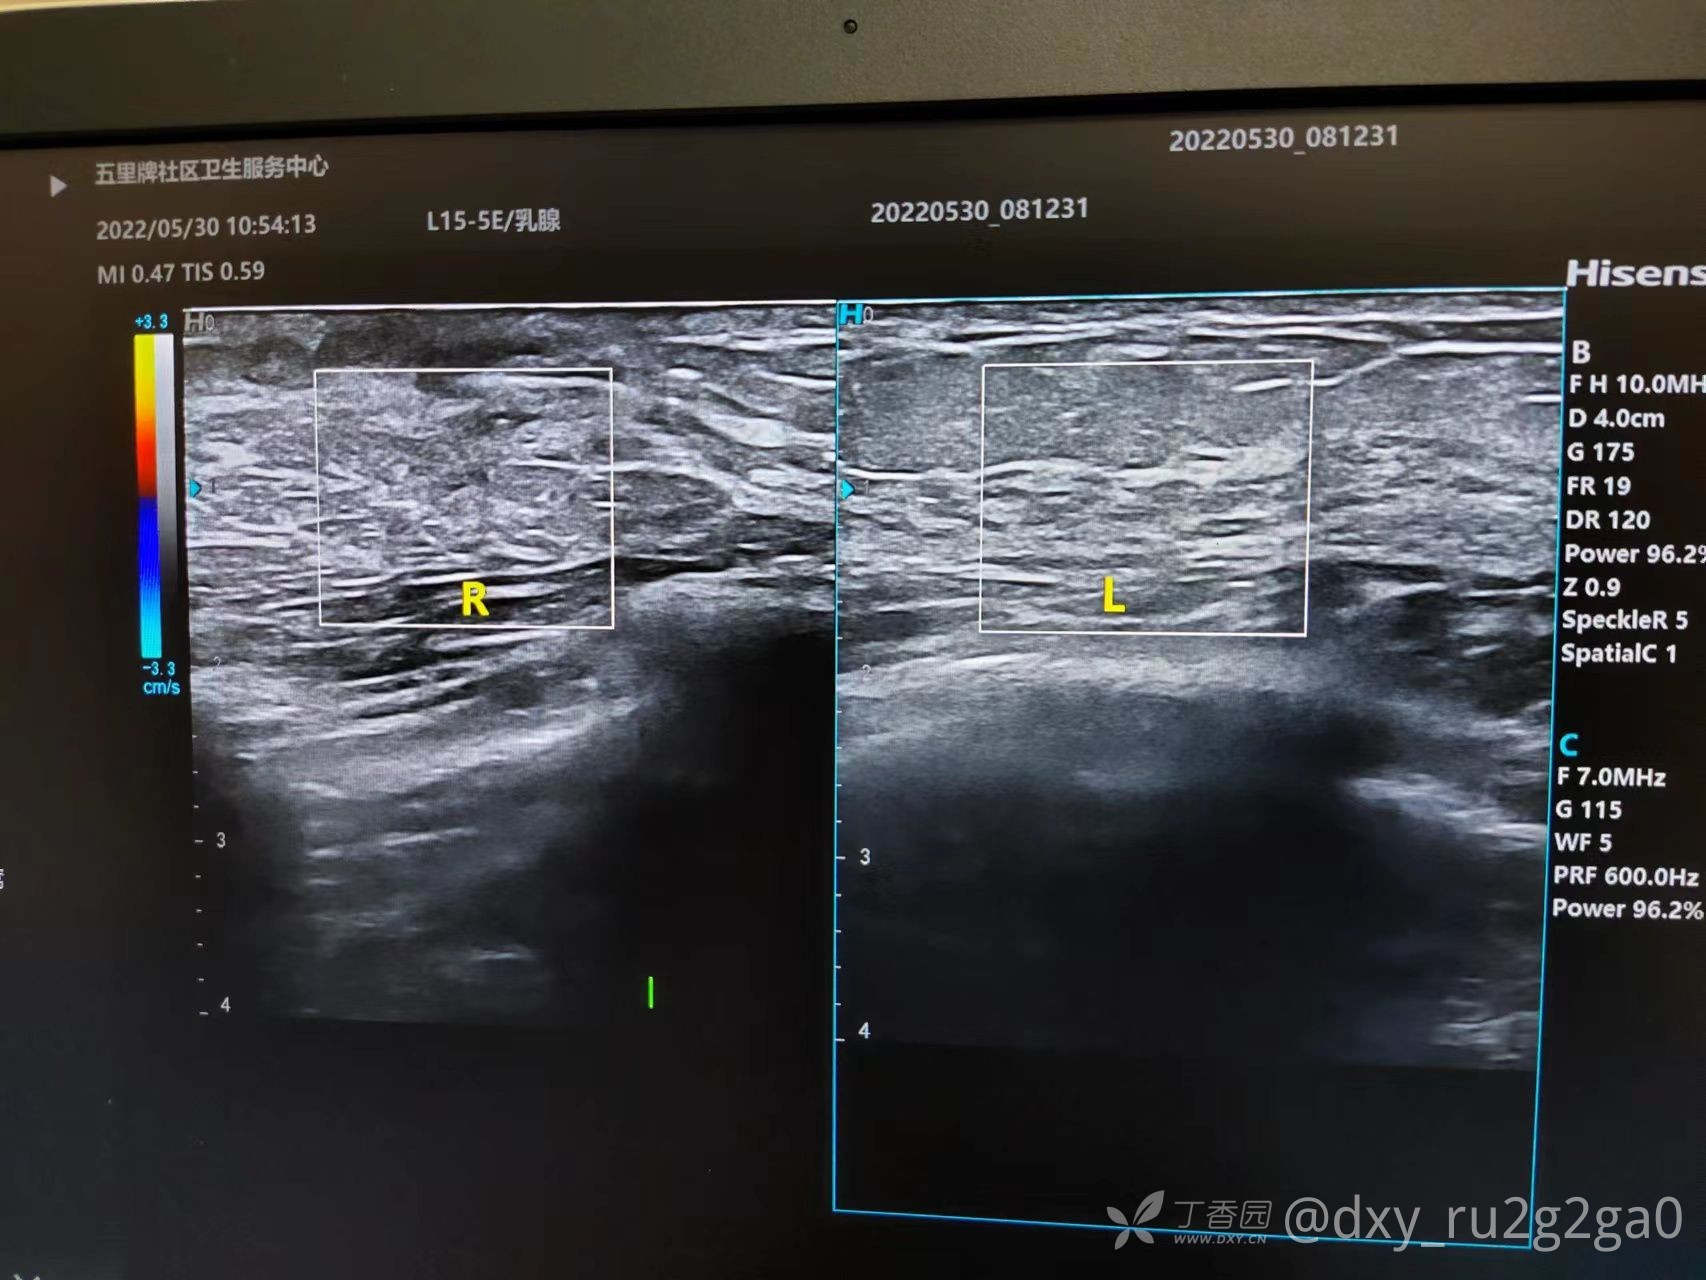

该病例21岁未婚 右胸偶感疼痛 如针刺样 触诊有肿块

img